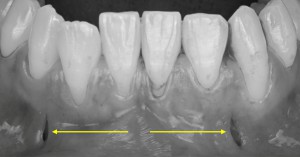

※下顎前歯の拡大写真

下あごの前歯部に注目すると、黒い線で示した部分が歯の上の部分(歯冠)と根の部分(歯根)の境目になります。

この境目よりも歯ぐきが下がっている状態がみられ、歯ぐきの退縮が起こっていることが確認できます。

※下顎の前歯の拡大写真

丸で囲った部分に注目すると、歯の根の形が歯ぐきの下にうっすらと浮き出て見える状態が確認できます。

このような所見は、歯ぐきや骨の厚みが比較的薄い可能性を示していると考えられます。

また、矢印で示した部分では、歯と歯の間の歯ぐき(歯間乳頭)がやや下がっており、**すき間が見える状態(いわゆるブラックトライアングル)**が認められます。

このように歯と歯の間の歯ぐきにも変化がみられる場合には、治療方法の選択や処置の内容を慎重に検討する必要があり、症例によっては外科的な処置が難しくなることがあります。